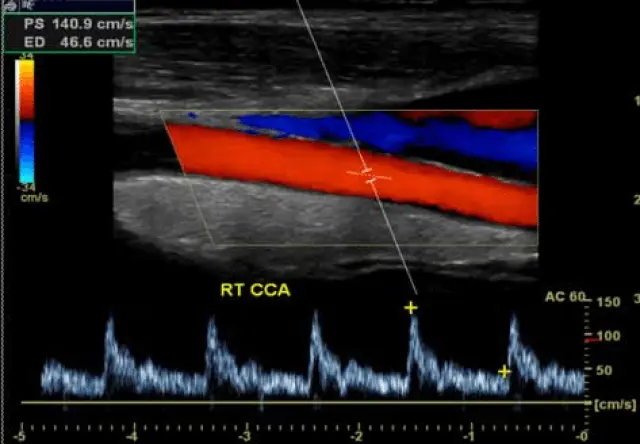

Duplex-Untersuchung der Halsgefäße

Hierbei werden die Arterien des Halses mittels Ultraschall untersucht. Besonders wichtig sind dabei diejenigen Gefäße, die das Gehirn mit Blut versorgen.

Der Duplex wird angewendet um zum Beispiel nach Ursachen des Schlaganfalls zu suchen. Auch kann untersucht werden, ob bereits Veränderungen an den Gefäße durch Risikofaktoren entstanden sind.  Bei zu hohen Cholesterinwerten ist die besonders Wichtig, um über eine Therapie zu entscheiden.